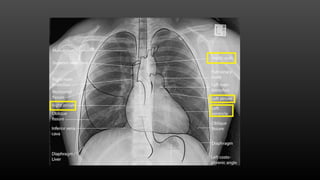

CHF with Right atrial enlargement

8 year old with shortness of breath

CHF with Rightatrial enlargement

8 year oldwith shortness of breath Pericardial effusion

• #32 Heart: size, when possible chambers Lungs: Pulmonary vasculature and congestion Bony abnormalities Airway

• #33 This is a rheumatic heart disease with right atrial enlargement